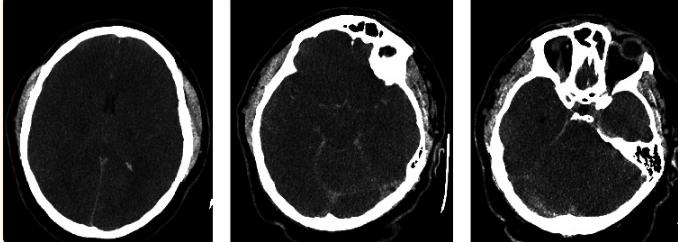

患者随后被转移到第三级护理中心。到达时,已经是心脏骤停后约1小时,神经学检查结果不佳。没有意识,瞳孔大小中等,没有角膜反射,没有眼脑反射,没有眼前庭反射,没有咳嗽和呕吐。行头部的计算机断层扫描(CT) (图2)。头部CT显示弥漫性脑水肿和假性蛛网膜下腔出血(图2a–2c)。在接下来几个小时里,尿量增加了900ml,钠含量增加,与尿崩症一致。

图2、头部CT (左至右)弥漫性脑水肿(a)和假性蛛网膜下腔出血(b,c)